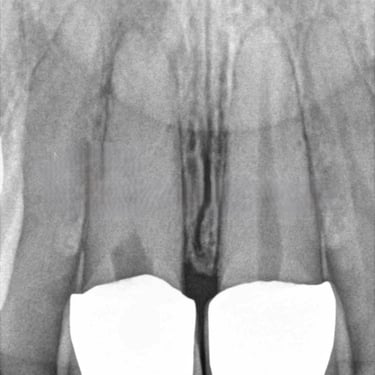

Reabsorción Interna

La reabsorción interna es la destrucción progresiva de la dentina desde el interior del diente hacia afuera, generalmente debido a un trauma o inflamación pulpar.

Los pacientes pueden notar un cambio de color en el diente.

Es necesario un tratamiento de conducto para detener el proceso y salvar el diente. Sin tratamiento, el diente puede debilitarse y fracturarse.